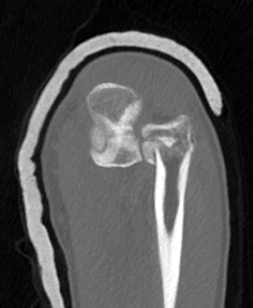

Elbow dislocation + olecranon fracture + radial head/neck fracture +/- coronoid fracture

- 85% coronoid process and 87% radial head fractures

- 5% LCL injuries